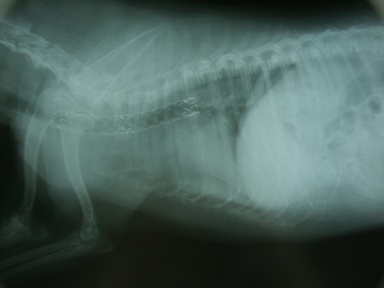

診断 気管虚脱+気管気管支軟化症

処置:Ultraflex Diamond留置(図11)

合併症:ステント破損(図12)したが、気管支拡張療法で気管開存(図13)。現在follow中(877日間)。

図11 症例2の第10病日。Ultraflex Diamondを胸部気管に留置。

図12 症例2の第18病日。ステントの破損。

図13 症例2の第45病日。気管支拡張療法の結果、気管が再び開存してきた。